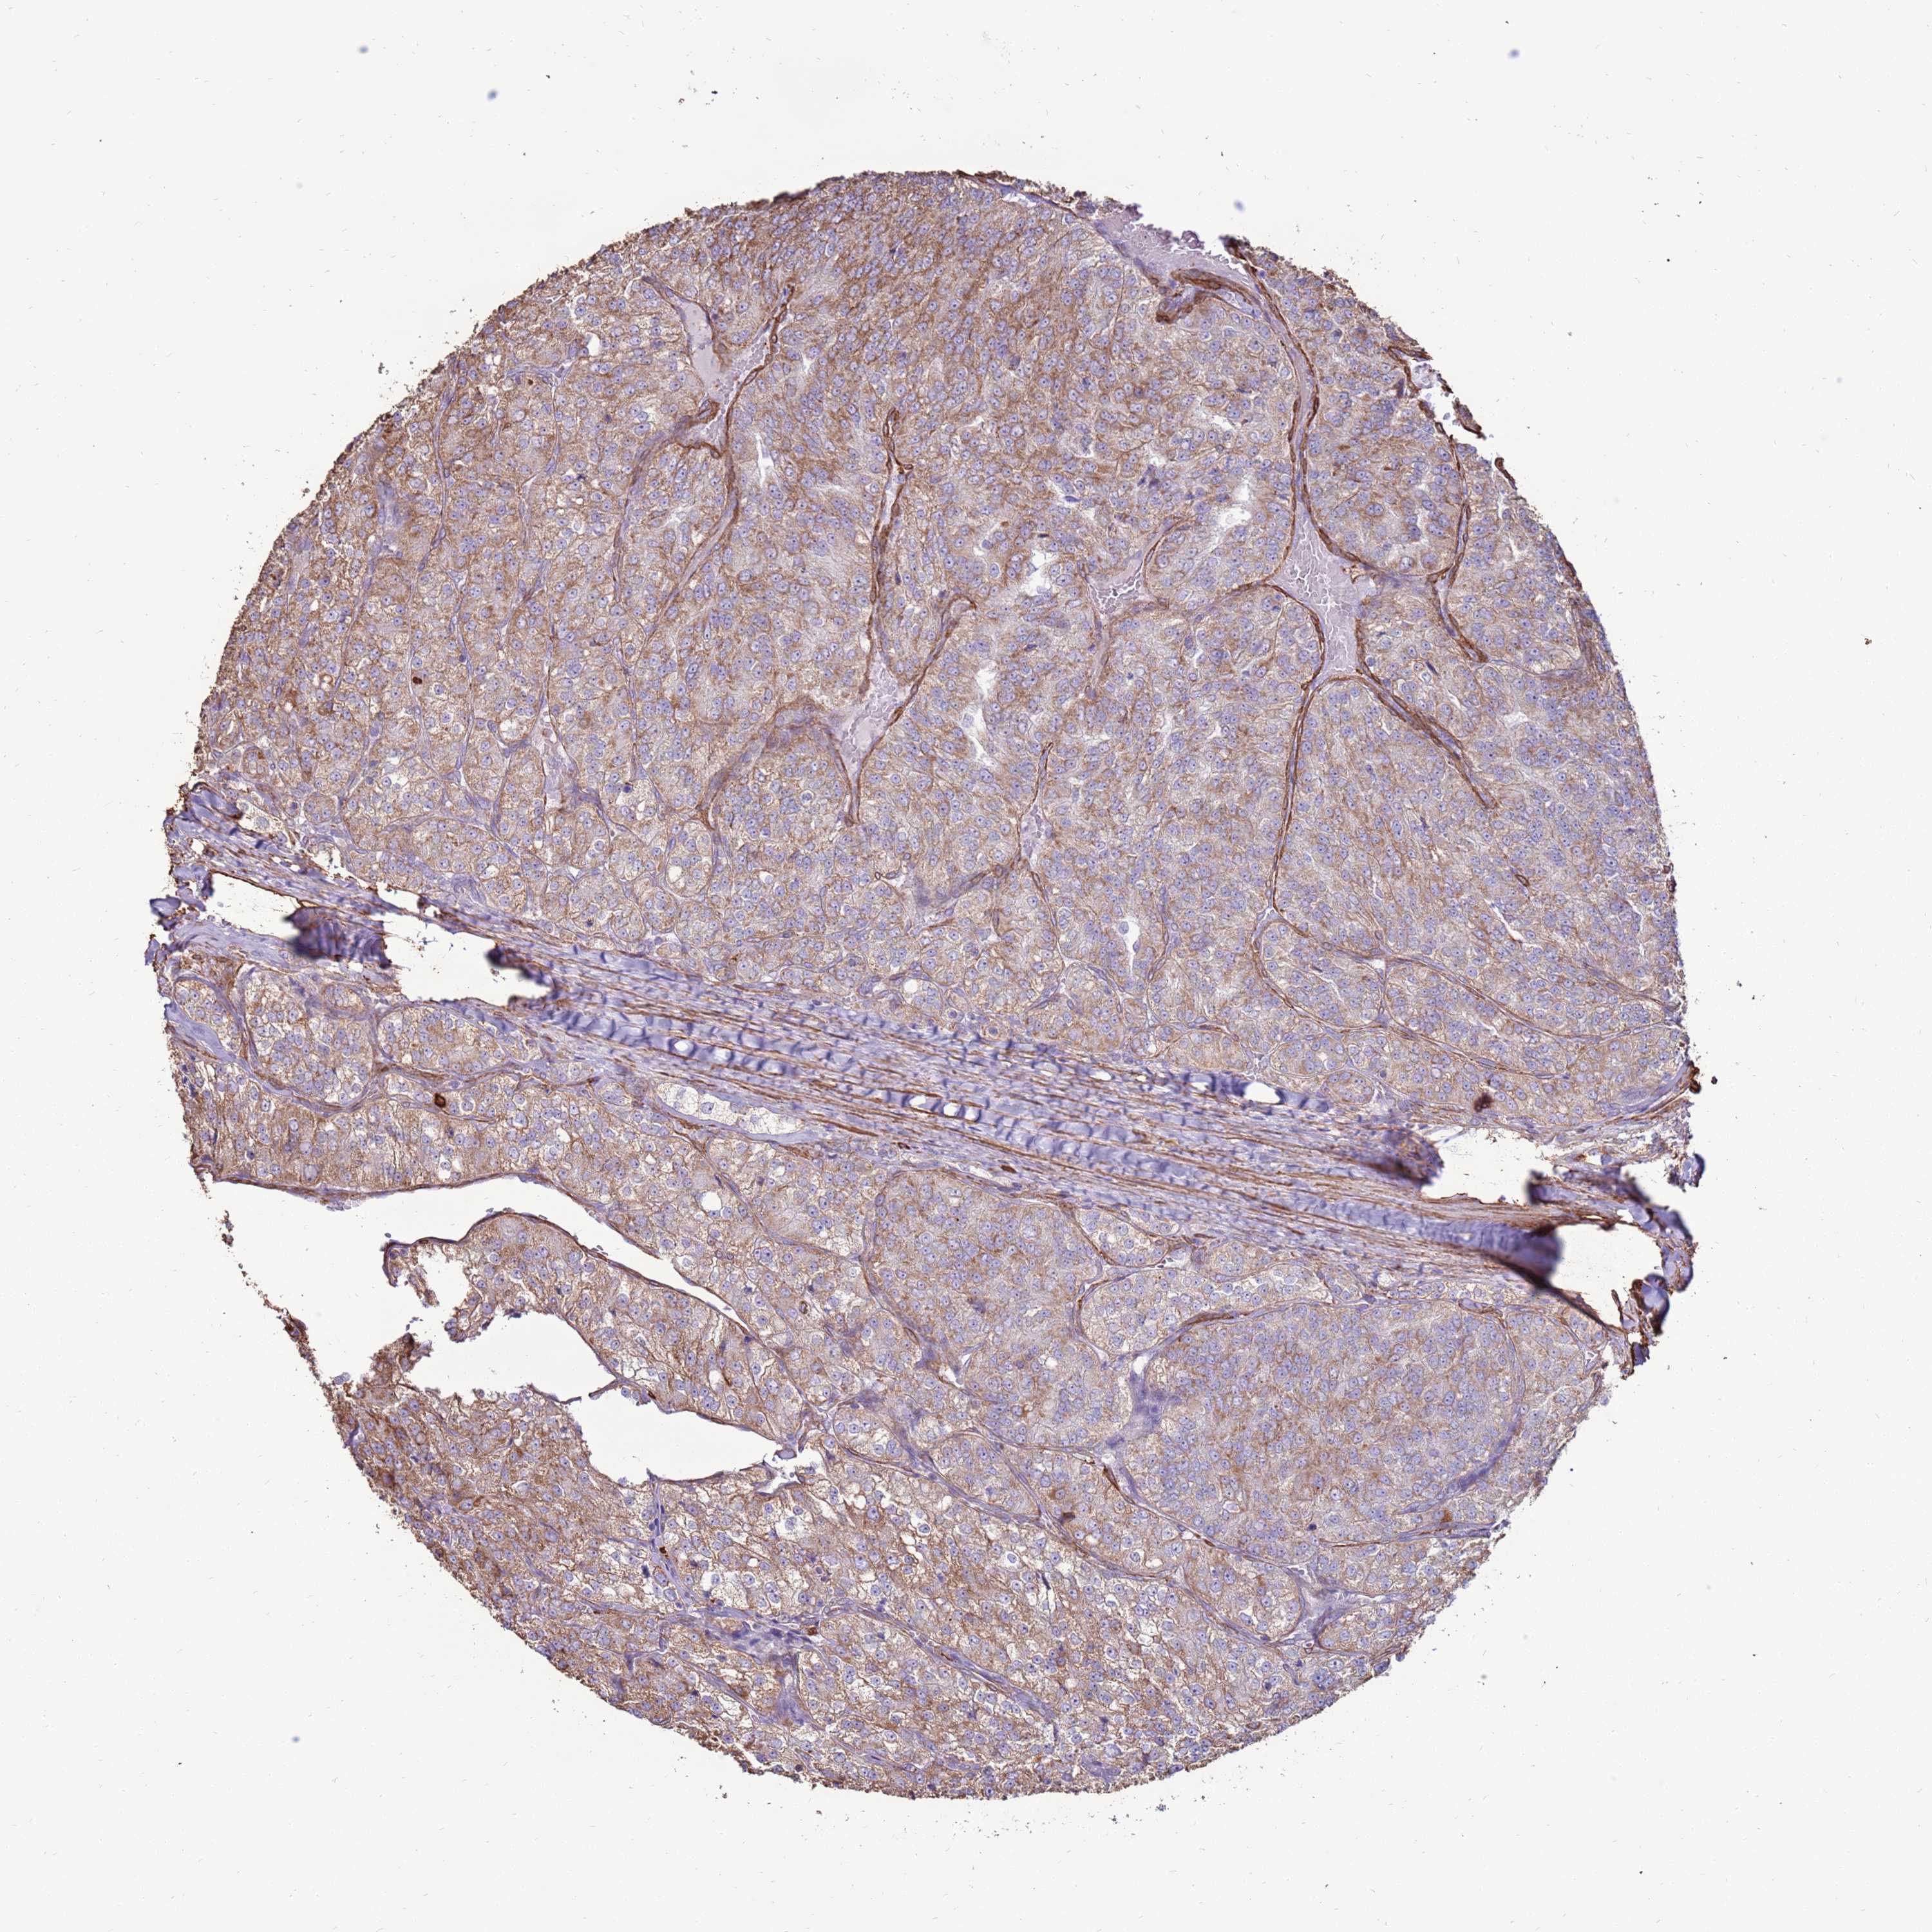

KIDNEY RENAL CLEAR CELL CARCINOMA (VALIDATION) - Interactive survival scatter ploti

The Survival Scatter plot shows the clinical status (i.e. dead or alive) for all individuals in the patient cohort, based on the same data that underlies the corresponding Kaplan-Meier plots. Patients that are alive at last time for follow-up are shown in blue and patients who have died during the study are shown in red.

The x-axis shows the expression levels (FPKM) of the investigated gene in the tumor tissue at the time of diagnosis. The y-axis shows the follow-up time after diagnosis (years). Both axes are complimented with kernel density curves demonstrating the data density over the axes. The top density plot shows the expression levels (FPKM) distribution among dead (red) and alive patients (blue). The right density plot shows the data density of the survived years of dead patients with high and low expression levels respectively, stratified using the cutoff indicated by the vertical dashed line through the Survival Scatter plot. This cutoff is automatically defined based on the FPKM cutoff that minimizes the p-score. The cutoff can be changed by dragging the vertical line or by entering a cutoff value in the square labeled "Current cut-off".

Under the Survival Scatter plot the p-score landscape (black curve; left axis) is shown together with dead median separation (red curve; right axis). Dead median separation is the difference in median mRNA expression between patients who have died with high and low expression, respectively. It is calculated as follows: median FPKM expression of dead patients with high expression - median FPKM expression of dead patients with low expression. This is intended to aid the user in visually exploring custom cutoffs and the associated p-scores and dead median separation.

Individual patient data is displayed and can be filtered by clicking on one or more of the category buttons on the top of the page. Categories describing expression level and patient information include: high, low, alive, dead, female, male and tumor stages. The scale of the x-axis can be toggled between linear and log-scale by clicking on the "x log" button. Mouse-over function shows TCGA ID, patient information and mRNA expression (FPKM) for each patient.

& Survival analysisi

Kaplan-Meier plots summarize results from analysis of correlation between mRNA expression level and patient survival. Patients were divided based on level of expression into one of the two groups "low" (under cut off) or "high" (over cut off). X-axis shows time for survival (years) and y-axis shows the probability of survival, where 1.0 corresponds to 100 percent.

DDX59 is not prognostic in Kidney Renal Clear Cell Carcinoma (validation)

Best expression cut offi

Based on the FPKM value of each gene, patients were classified into two groups and association between prognosis (survival) and gene expression (FPKM) was examined. The best expression cut-off refers the FPKM value that yields maximal difference with regard to survival between the two groups at the lowest log-rank P-value. Best expression cut-off was selected based on survival analysis .

When clicking on this number, the vertical dashed line indicating cut-off, the interactive survival plot, and the Kaplan-Meier curve will be adjusted to show results based on the best expression cut-off.

: 25.13

Median expressioni

Median expression refers to the median FPKM value calculated based on the gene expression (FPKM) data from all patients in this dataset. When clicking on this number, the vertical dashed line indicating cut-off, the interactive survival plot, and the Kaplan-Meier curve will be adjusted to show results based on the median expression.

: N/A

Median follow up timei

Median follow up time refers to the median time (years) after diagnosis with this type of cancer, based on clinical data from all patients in this dataset.

P scorei

Log-rank P value for Kaplan-Meier plot showing results from analysis of correlation between mRNA expression level and patient survival.

N/A

5-year survival highi

5-year survival for patients with higher expression than the expression cutoff.

For melanoma and glioma, 3-year survival is shown.

5-year survival lowi

5-year survival for patients with lower expression than the expression cutoff.

TCGA RNA samplesi

RNA-seq data is reported as average FPKM (number Fragments Per Kilobase of exon per Million reads), generated by the The Cancer Genome Atlas (TCGA) .

Normal distribution across the dataset is visualized with box plots, shown as median and 25th and 75th percentiles. Points are displayed as outliers if they are above or below 1.5 times the interquartile range. FPKM values of the individual samples are presented next to the box plot.

Average pTPM 25.7

Number of samples 100